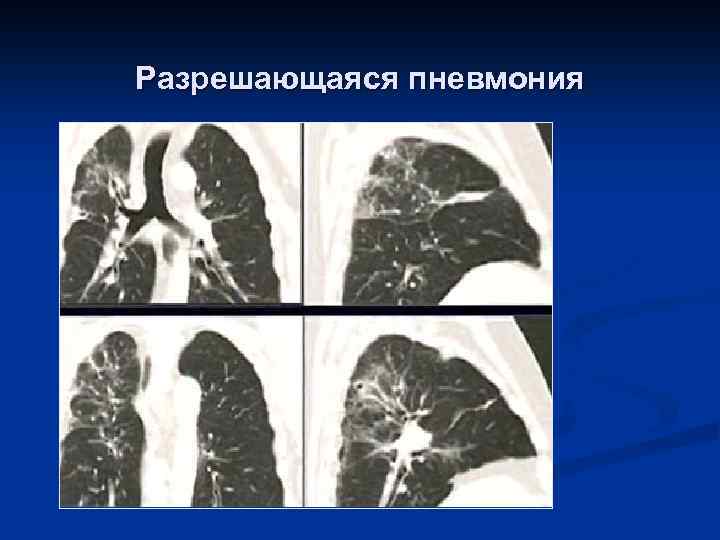

Разрешающаяся пневмония